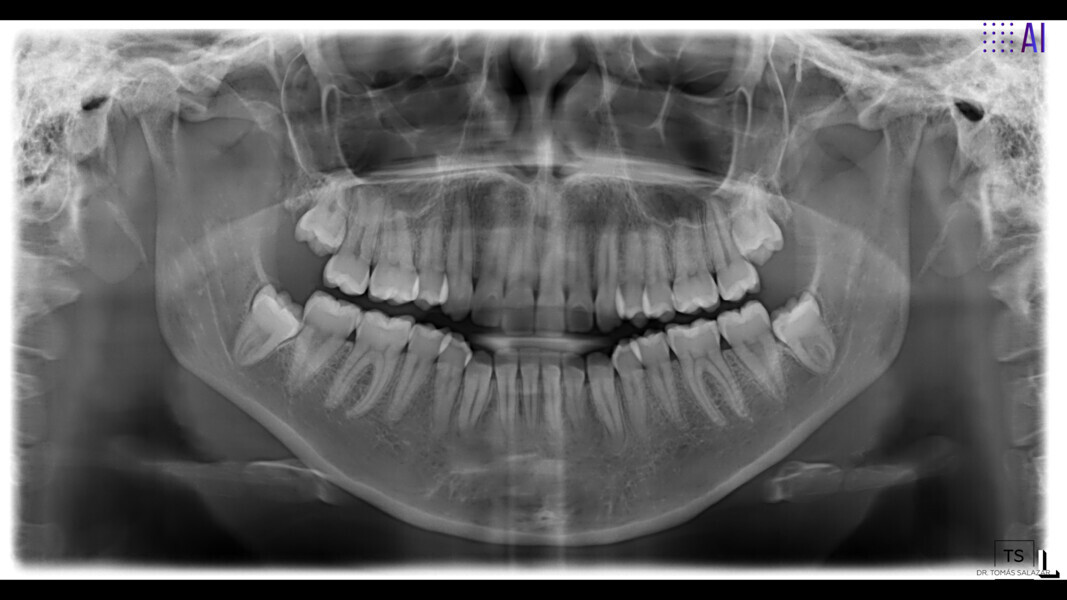

The 23-year-old dolichofacial female patient complained of not being able to chew properly. Facial examination showed a convex profile, an enlarged lower facial height, and a skeletal Class III malocclusion (Figs. 1–3). Intra-oral examination revealed an Angle Class III right subdivision malocclusion, anterior open bite, no overjet and a maxillary dental midline deviated about 3 mm to the right compared with the mandibular dental midline (Fig. 4). The panoramic radiograph confirmed previous extraction of the maxillary right first premolar and the presence of all four third molars (Figs. 5 & 6).